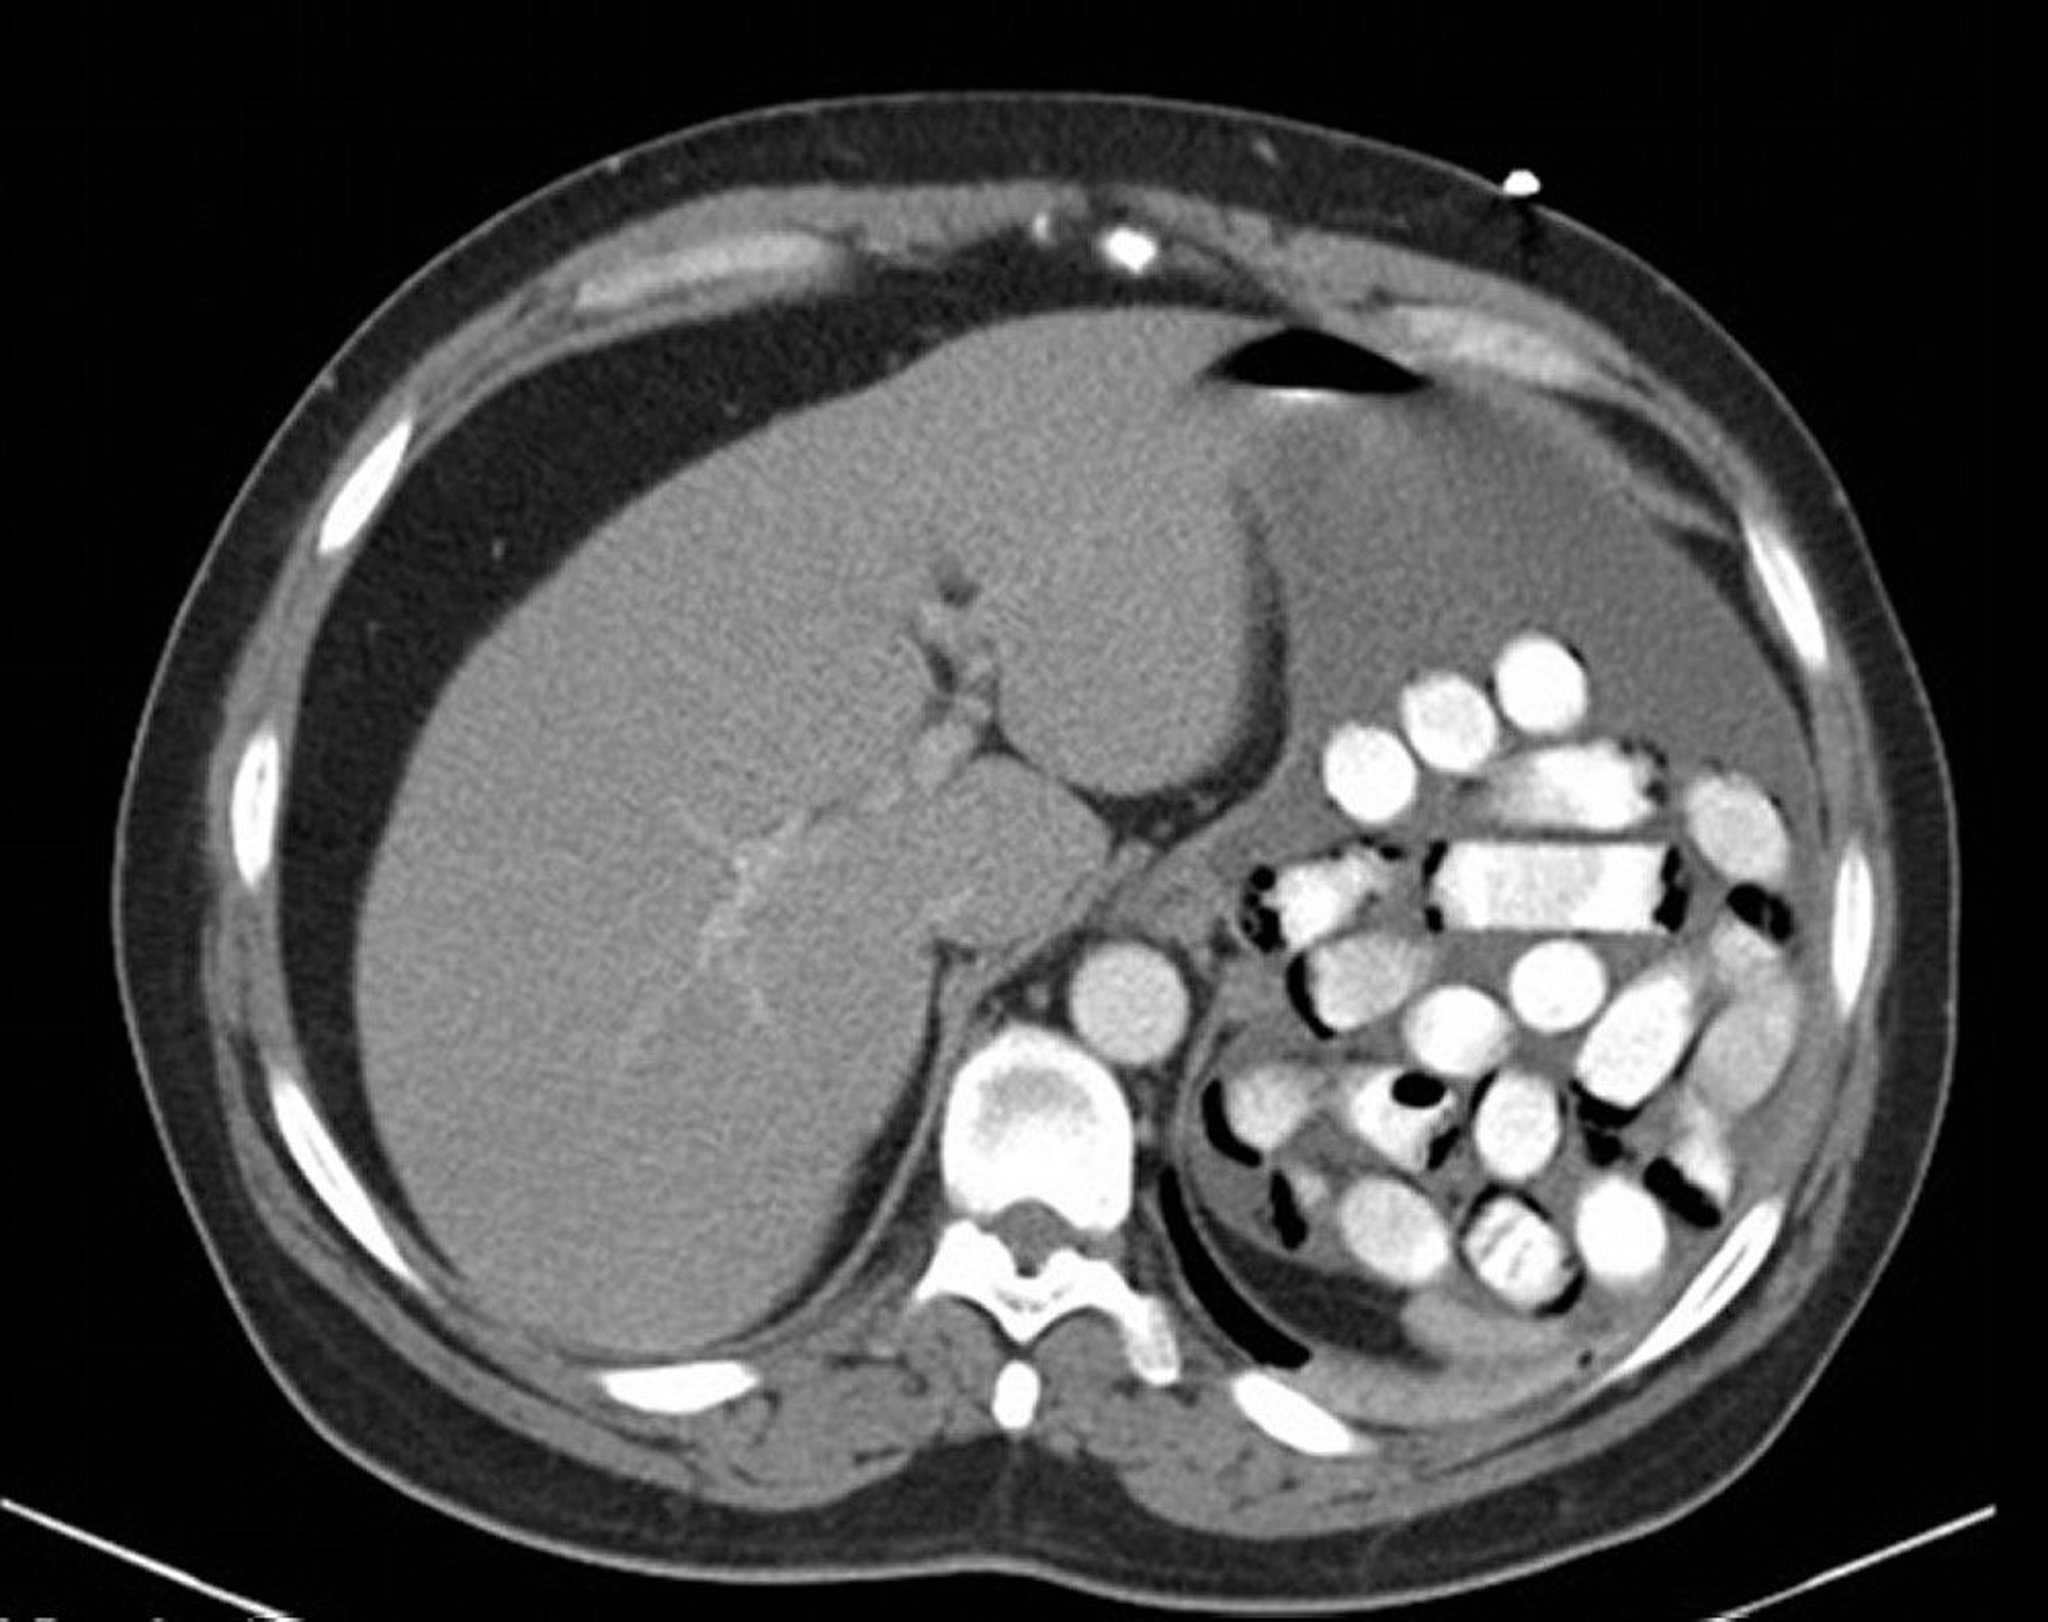

Gastric Foreign Body (CT Scan)

This image shows drug packets in the stomach.

Image provided by Alan Gingold, DO.